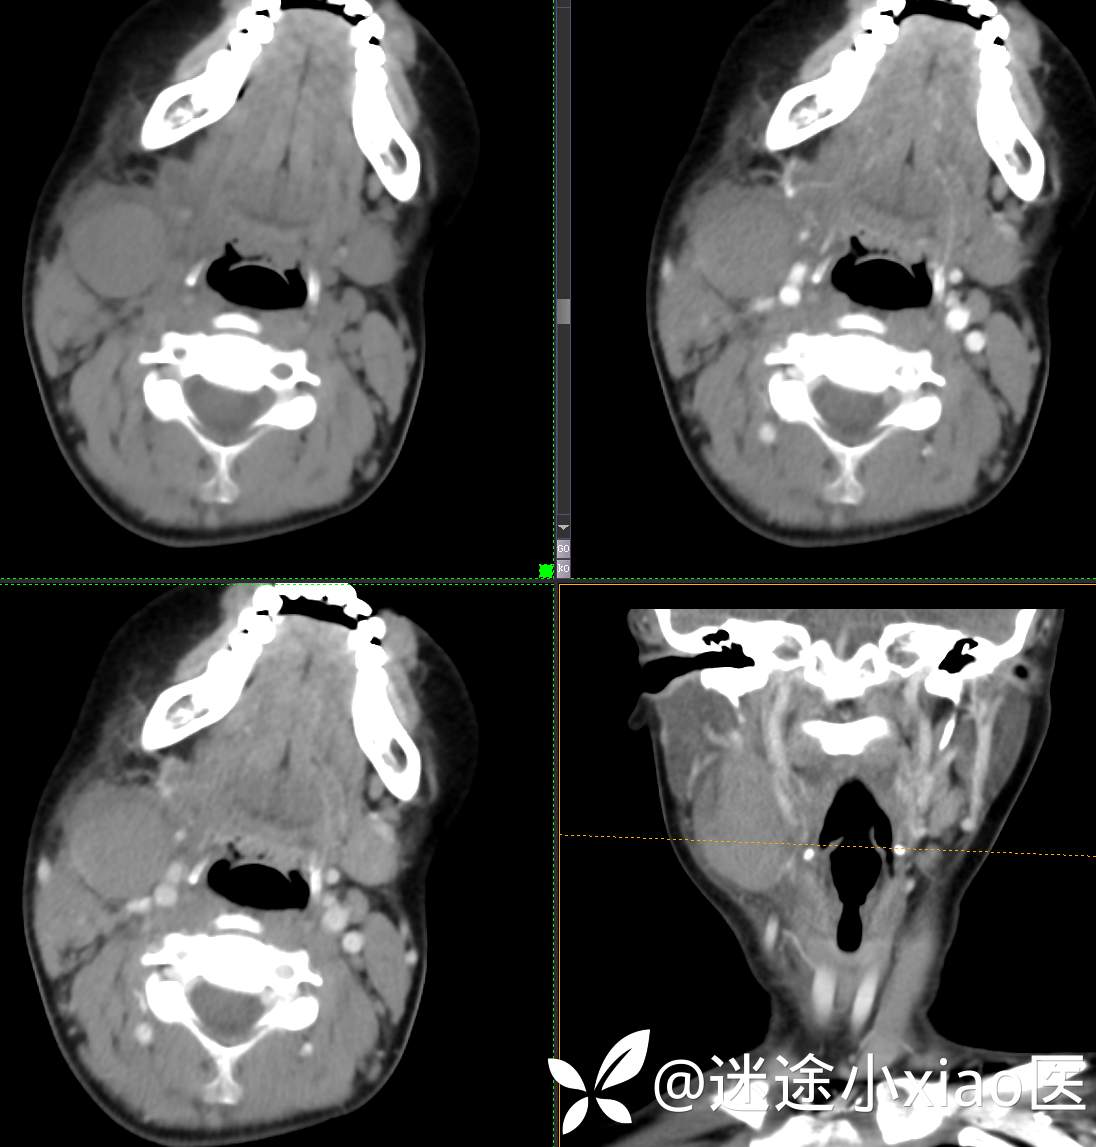

头颈组16:青少年女性,发现右颈部肿物半月余,感染?肿瘤?

现病史:患者半月余前无明显诱因下发现右颈部肿物,大小4.2*2.1cm,局部无红肿,皮温正常,有压痛,感头晕头痛,无其他不适。查甲状腺及颈部淋巴结B超提示:双侧甲状腺多发结节;右侧多发肿大淋巴结。初步诊断为“淋巴炎”,予“头孢类”抗生素抗感染治疗12天(具体药物不详),自觉肿块胀痛缓解,头晕头痛症状仍存。